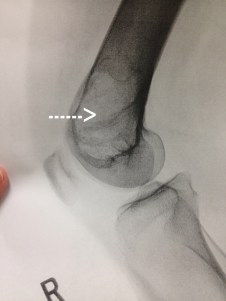

When the PA came into the room, he asked about the pain I have been having and showed me the x-ray that clearly displays my kneecap a little left of center. But then he explained that they also saw something else of concern–I have a tumor in my femur (thigh bone) where it connects into the knee joint. He showed me the x-ray which clearly shows a mass (see the area where the arrow points to). So not expecting news like this, I was in shock. And of course the place that my mind goes is “what does this mean for the Ironman?” When the doctor came in he explained what he thinks it is–a giant cell bone tumor which I probably have had for a long time. He said most people find out about it when their bone breaks so to find it before then is a good thing. He also said that most of the time they are benign, but I would still need surgery to take it out and then bone grafting to replace the bone that has been lost to the tumor. He explained that I would need an MRI, then a nuclear bone scan and then to see an orthopedic oncologist (the closest one being in New Orleans). But what about running and what about the race I have been training for this past year? He said that I could keep swimming and biking, but really didn’t want me to keep running. I explained that I was training for the Ironman and my race was in 6 weeks–even as I type this I realize the absurdity of that statement, but we all know there is a little crazy in those of us willing to take on the Journey to the Ironman.